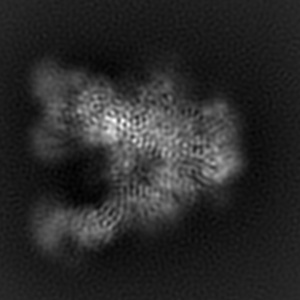

Cryo-EM structure of EDC-crosslinked ConM SOSIP.v7 (ConM-EDC) in complex with bNAb PGT122

Single-particle3.85 Å

Sample: EDC-crosslinked ConM SOSIP.v7 in complex with PGT122 Fab